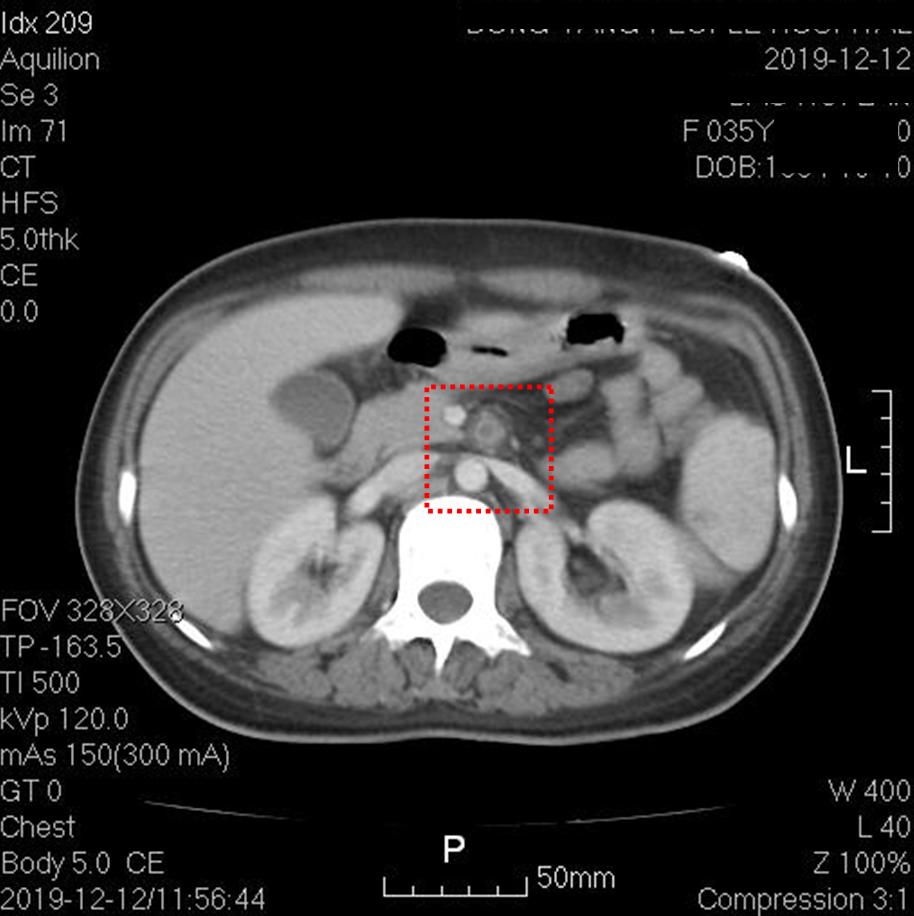

上图红框内为肠系膜上动脉根部,可见管腔内未增强,动脉周边组织稍模糊,提示存在炎症改变。其他层面肠系膜上动脉通畅。